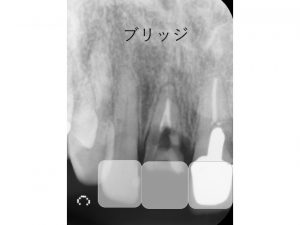

以下は被せ物を撤去し、根が折れているのを直視で確認した後に撮ったレントゲン写真です。

一つはブリッジです。

ブリッジは欠損部の両側の歯を削り、被せ物を行う治療です。